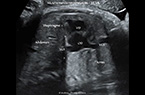

Grossesse extra-utérine tubaire distale droite, évolutive, de 9 SA et 2 Jours d'âge - Activité cardiaque et mouvements embryonnaires sont présents - coupe transverse de l'utérus Grossesse extra-utérine tubaire distale droite, évolutive, de 9 SA et 2 Jours d'âge - Activité cardiaque et mouvements embryonnaires sont présents - coupe transverse de l'utérus Grossesse extra-utérine tubaire distale droite, évolutive, de 9 SA et 2 Jours d'âge - Activité cardiaque et mouvements embryonnaires sont présents - coupe transverse de l'utérus